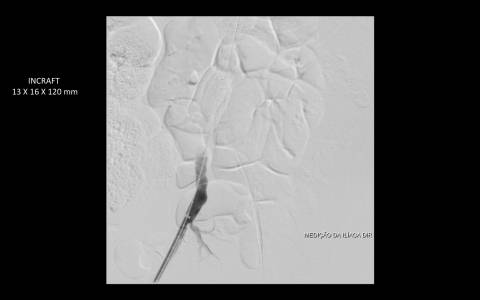

O estudo de angiotomografia evidenciou que as artérias iliacas externas e femorais apresentavam-se com muitas calcificações e ponto de estenose mais crítica em artéria ilíaca comum direita. Diante dos achados de imagem, foi optado por endoprotese de aorta abdominal de baixo perfil (Incraft – Cordis).